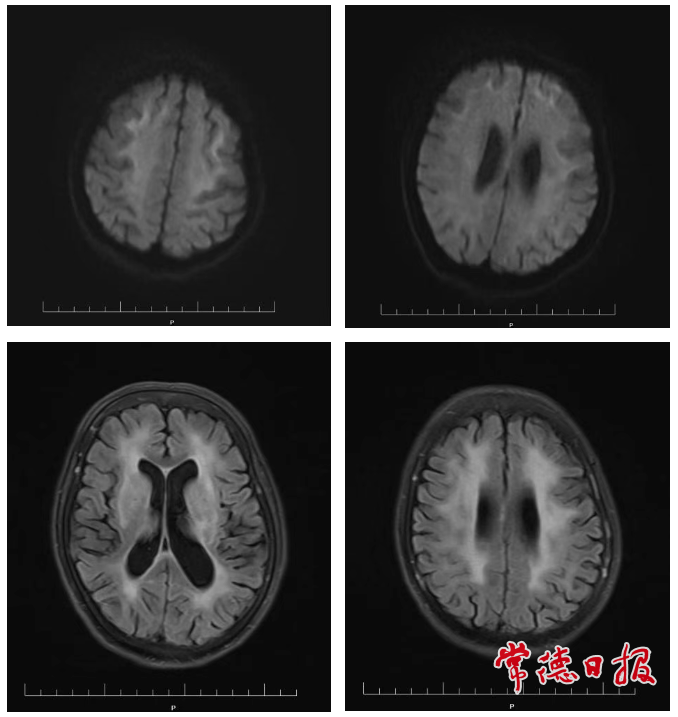

關(guān)鍵證據(jù)出現(xiàn)在次日完成的頭部磁共振檢查中:圖像清晰顯示患者腦白質(zhì)存在典型的彎曲條帶狀異常信號,即診斷NIID高度特異性的“綢帶征”。結(jié)合患者發(fā)作性腦病、進(jìn)行性認(rèn)知下降、瞳孔縮小等臨床表現(xiàn),NIID的診斷得以確立。